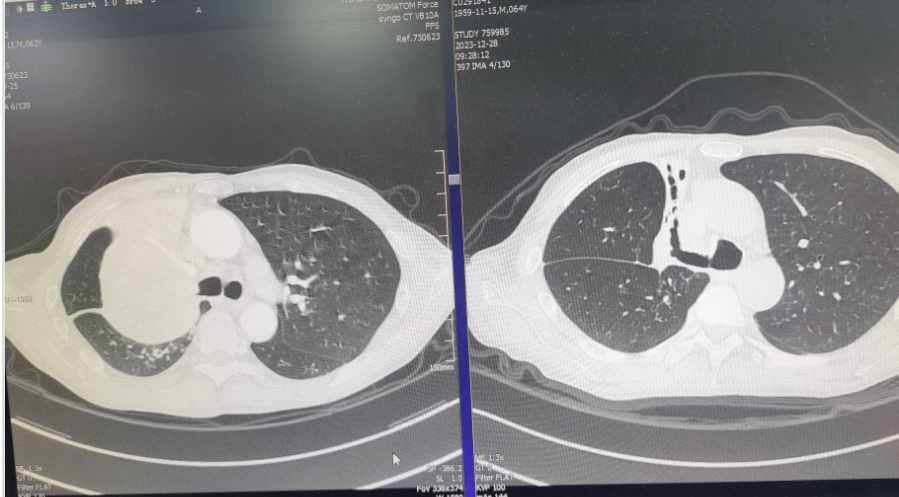

右上肺被「断气」,原本该坍缩,但事实上却呈现出膨胀实变。进一步检查发现,原来右上肺内滋生了大量结核菌,导致大量分泌物、粘连充斥其中,在出口被「新生物」堵死的条件下,右上肺就只能不断膨胀、实变、毁损。

而接下来,一个个坏消息,不断来雪上加霜:首先,这些结核菌在检测中发现具有耐药性。也就是说,谢师傅患上了被称为「不死癌症」的耐多药结核病,另外,新生物也被病理诊断为肺鳞癌,且处在 IIIA 期(局部晚期)。

通过上述两种方法的巧妙应用,谢师傅的肿瘤瘤体逐渐吸收、缩小,四个月后,仅残余少量肿瘤组织。

因为堵塞支气管的肿瘤消除,右上肺内的支气管逐渐畅通,脓液、分泌物逐渐排出,留下一个千疮百孔,已经毁损掉的右上肺。